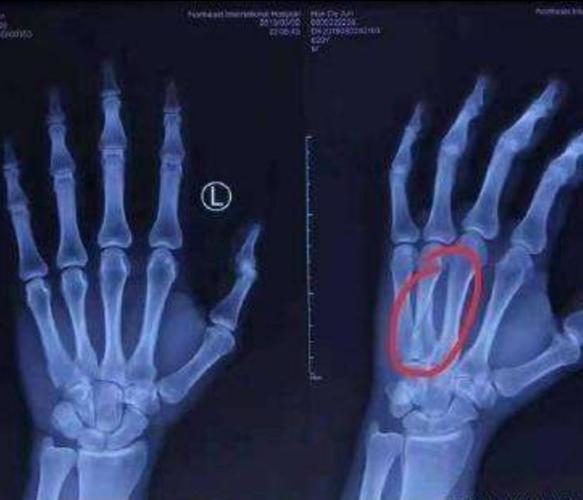

掌骨骨折:直接暴力伤易横行骨折,间接外力或扭转时易斜形或螺旋形骨折

近节指骨螺旋形骨折:拉力螺钉